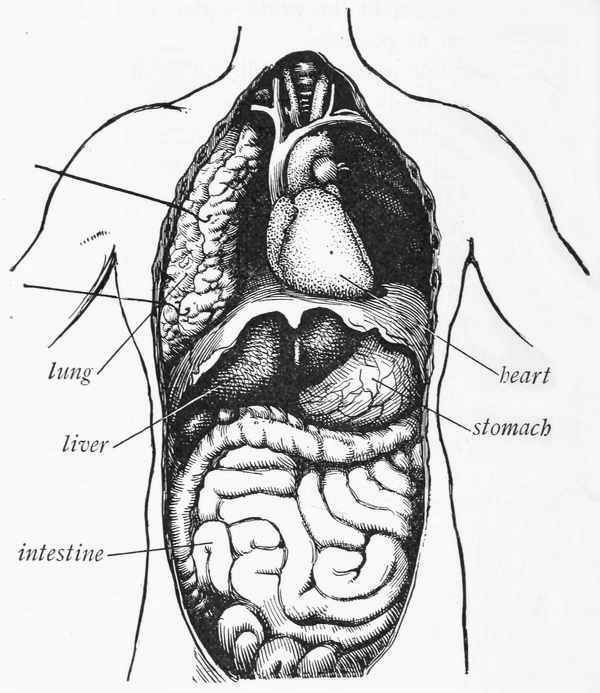

These bodies of ours are built somewhat like automobiles. An automobile is made up of a framework, wheels, body, gasoline tank, engine, and steering-gear. The human body has much the same form of construction. We have a frame, which is made of the bones of the body.[5] We have arms and legs, which correspond to the wheels of the automobile. We have many little pockets in our bodies in which fat is stored, and these little pockets answer to the gasoline tank of the automobile. We have an engine which, like the automobile engine, is made up of many parts; and we have a head or brain, that plays the same part as the steering-gear of the automobile.

You can scratch some of the paint from your automobile and the machine will work just as well as ever. Apparently no harm has been done, but an opening has been made through which moisture and germs can enter and cause the wood to rot and the iron to rust. You can remove certain parts of the automobile and still the machine will do its work; but you cannot take away too much of any one part without weakening the automobile, and if certain parts are missing (such as the sparker, the battery, or the steering-gear), the usefulness of the machine is destroyed. So it is with the body. You can scratch off some of the skin and not do any apparent harm, but you have made an opening through which germs may get into the body. You can remove certain parts of the body, such as the arm or leg, and still the body will do efficient service. But there are certain parts of the body that are necessary to life, just as certain parts of the automobile are necessary to the usefulness of the machine. You cannot remove the heart and live; you cannot remove the brain and live.

The cells of the body need oxygen, and the only way we can give it to them is by means of air. Every time we take air into our lungs we are giving oxygen to the red corpuscles or cells in the blood, which distribute it to the other cells in the body. The air that goes into our lungs, if it is fresh and pure, contains a great deal of oxygen and a very little of another gas called carbon dioxid. The air that comes out of the lungs contains a very little oxygen and a great deal of carbon dioxid. The blood not only takes the oxygen out of the air, but gives carbon dioxid to the air. This carbon dioxid is very poisonous, and would kill the cells if it remained in the blood; hence we should never breathe the same air twice. There is no lack of fresh air in the world, and no excuse for anyone's ever breathing air that is not pure.